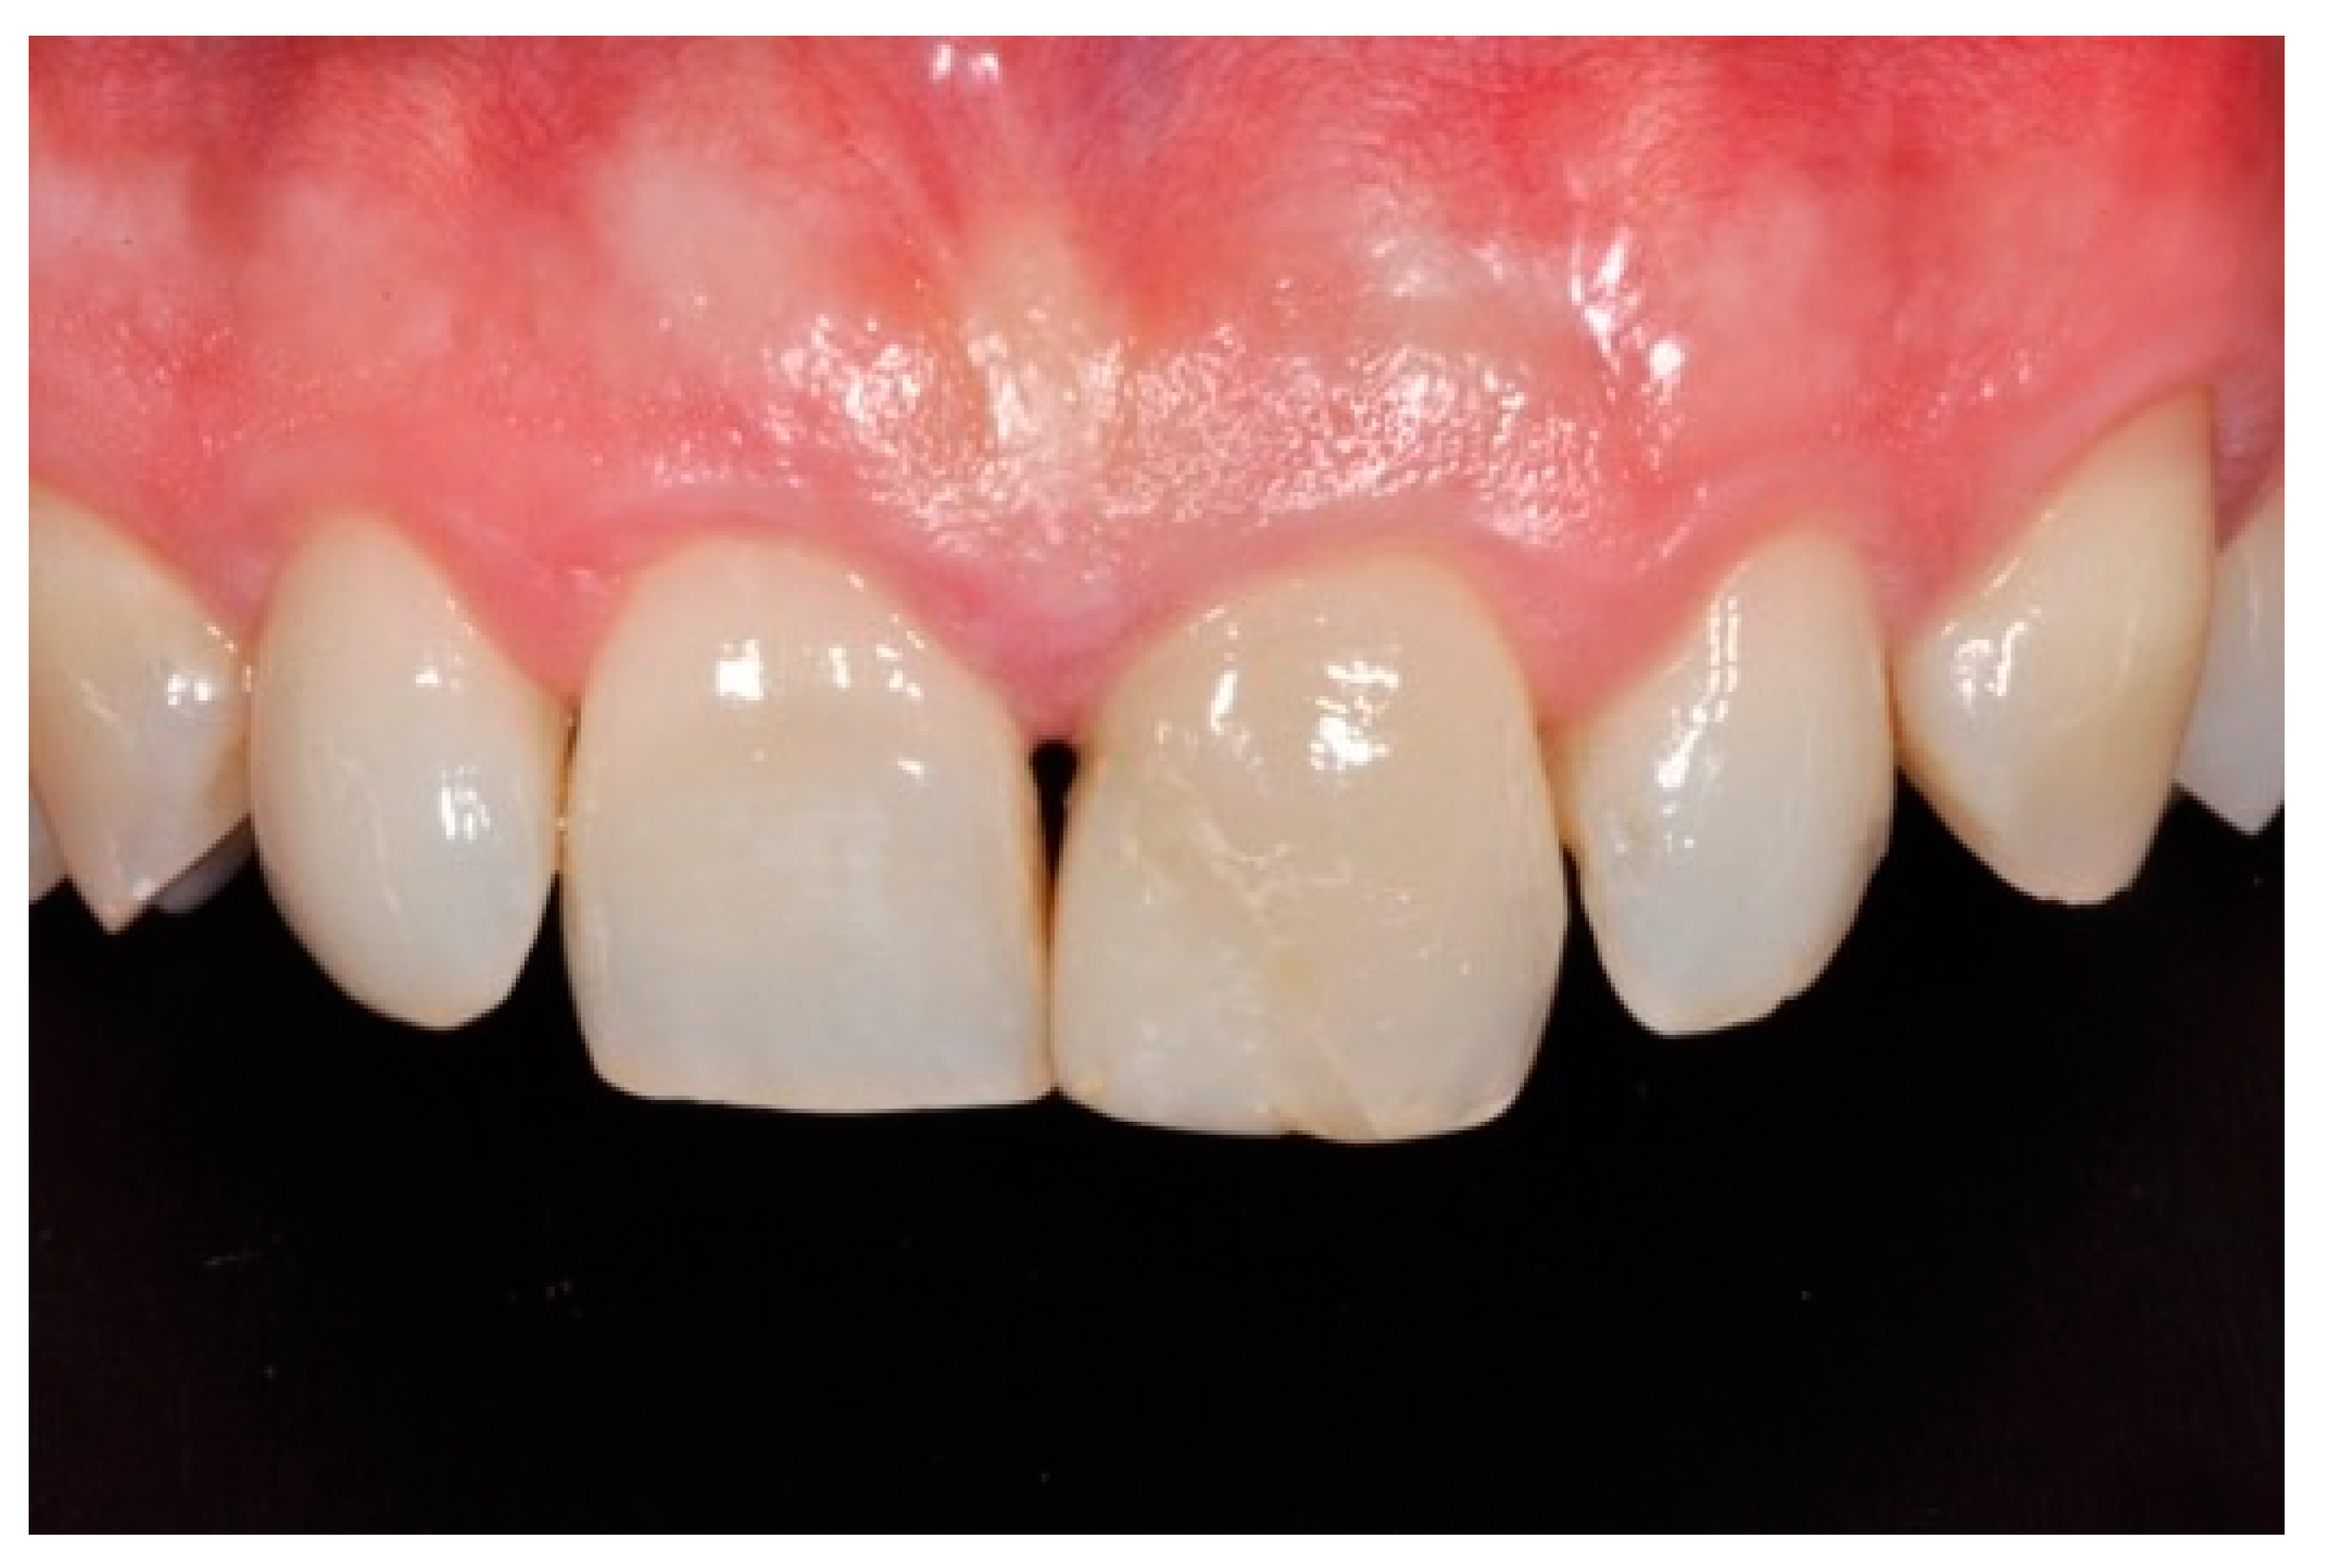

Figure 18.

Five years post-operative.

Figure 19.

Five years post-operative x-ray.